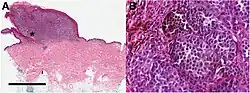

Lymph node with almost complete replacement by metastatic melanoma. The brown pigment is a focal deposition of melanin. -

Histopathology of a metastatic melanoma to a lymph node, H&E stain, showing poorly differentiated cells -